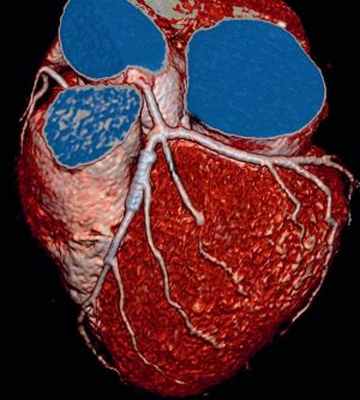

Коронарография (ангиография). Этот метод выявляет суженные или закрытые (окклюзированые) коронарные артерии. Жидкий контраст вводят в артерии сердца, через специальное устройство (катетер), который подводят к артериям, через прокол (пункцию) в бедренной артерии. Контрастное вещество заполняет артерии, артерии становятся видимыми на рентгеновских снимках и это позволяет точно определить характер, степень и место сужения коронарных артерий.

Кроме того через проведенный катетер, доктор может устранить стеноз в коронарной артерии, выполнив ангиопластику. Ангиопластика выполняется при помощи маленького баллона, который вводится в пораженный участок коронарной артерии, там он раздувается и тем самым устраняется сужение в артерии. В большинстве случаев необходимо применение внутрисосудистых стентов. Это позволяет снизить частоту повторного сужения в коронарной артерии.